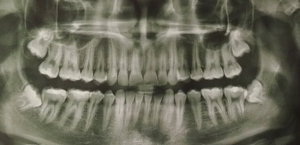

Нижняя правая восьмерка. Сам зуб не беспокоит, капюшон не мешает, но бывает из-под капюшона вытекает гной. Сказали надо удалять, но я что-то побаиваюсь, т.к. зуб целиком находится в костной ткани и близко к нижнечелюстному каналу.

Есть ли такая необходимость в его удалении, и насколько сложным и опасным оно будет?

Вам необходимо удалить все зубы мудрости. С 48 зубом рекомендую обратиться в ЧЛХ, так как Вы правы, корни данного зуба находятся в канале и после удаления продолжительное время у Вас будет парестезия (онемение). Но удалять крайне необходимо по причине того, что он повредит седьмой зуб, что в Вашем случае при отсутствии 46 будет очень нежелательно.